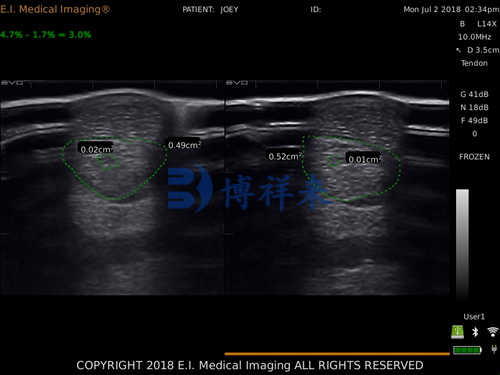

d. Image Acquisition: Adjust gain, depth, and focus to optimize the image. Tendons should appear as a linear, fibrillar pattern in longitudinal views and a round to oval, echogenic structure in transverse views. Identify any areas of hypoechogenicity (dark regions), fiber disruption, or swelling.

Tendon lesions typically appear as areas of decreased echogenicity (dark areas) with disrupted fiber alignment. Important diagnostic parameters include:

Lesion size (measured in both planes)

Percentage of cross-sectional area affected

Echogenicity (anechoic, hypoechoic, or mixed)

Fiber pattern (linear, disrupted, or chaotic)

Presence of tendon sheath effusion